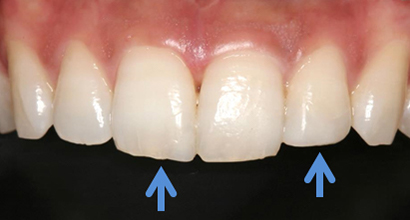

ダイレクトボンディング症例1

前歯がかけた

術前

転倒して前歯がかけてしまい(青矢印)できるだけ削らない治療ダイレクトボンディングを希望して来院されました

ダイレクトボンディング治療後